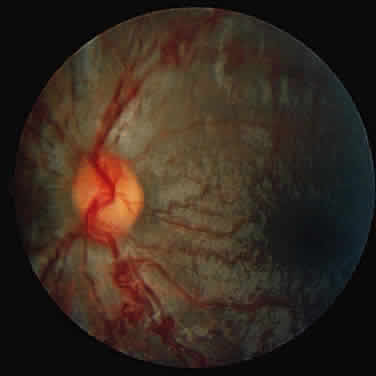

Progressive diffuse punctate stromal corneal opacities occur in all patients. They may conceal retinal degeneration and result in progressive visual loss.14,15 When the retina can be evaluated, a retinitis pigmentosa-like picture indistinguishable from other forms of heredofamilial retinal pigmentary dystrophies usually is present. The electroretinogram is diminished or nonrecordable.16 Glaucoma is relatively rare17 but has been reported in some patients.14,18 Optic nerve head swelling and optic atrophy are common10 (Fig. 2). Congenital cataracts occasionally have been observed.19

Fig. 2. Optic nerve head and peripapillary elevation in a patient with Hurler syndrome (MPS I-H).